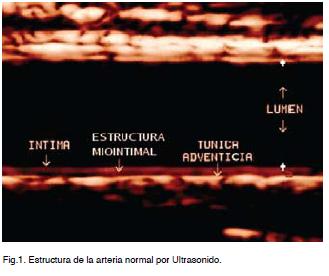

La pared arterial es el órgano blanco de esta enfermedad. Por medio del ultrasonido es posible en forma confiable, reproducible, no invasiva y de bajo costo el diagnóstico morfoestructural arterial a nivel de arterias fácilmente accesibles en una población aparentemente sana (Figura 1).

Comprende la medición del espesor íntima media a nivel carotideo, diámetros arteriales y la descripción anatómica de trayecto y ángulo de división. Búsqueda de lesiones (placas) y definición de su topografía, sus características morfológicas y el grado obstructivo (10-14).